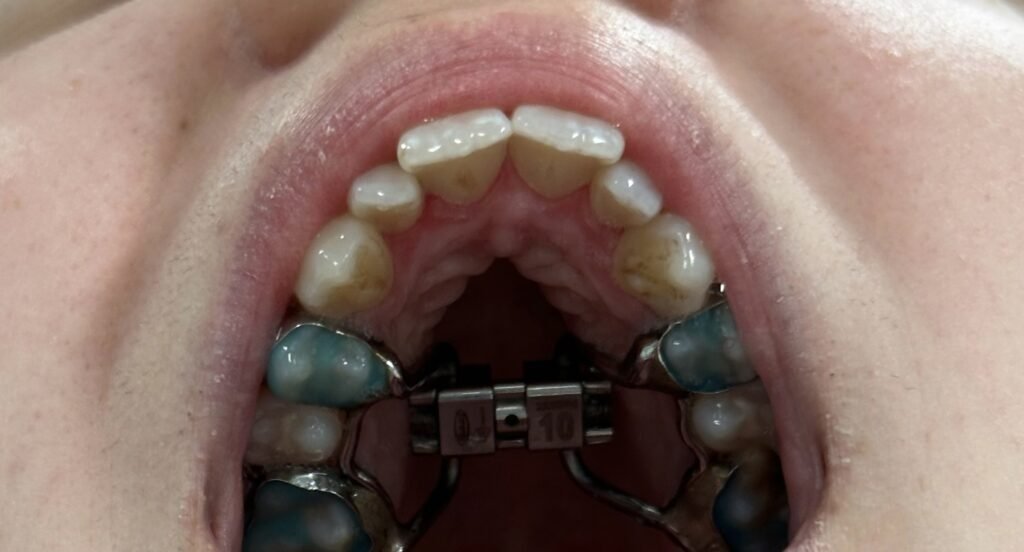

A cirurgia de expansão maxilar, após a adolescência, é realizada sob anestesia geral. O procedimento envolve a aplicação de um dispositivo chamado expansor palatino, que é colocado no céu da boca do paciente, dias antes da cirurgia, pelo seu Médico Dentista. Durante a cirurgia é feita uma osteotomia (corte) da sutura palatina que irá permitir a expansão do maxilar. Este expansor é ajustado gradualmente ao longo de alguns dias para separar as duas metades do maxilar, promovendo o alargamento ósseo.

Antes, durante e depois da expansão maxilar cirurgicamente assistida